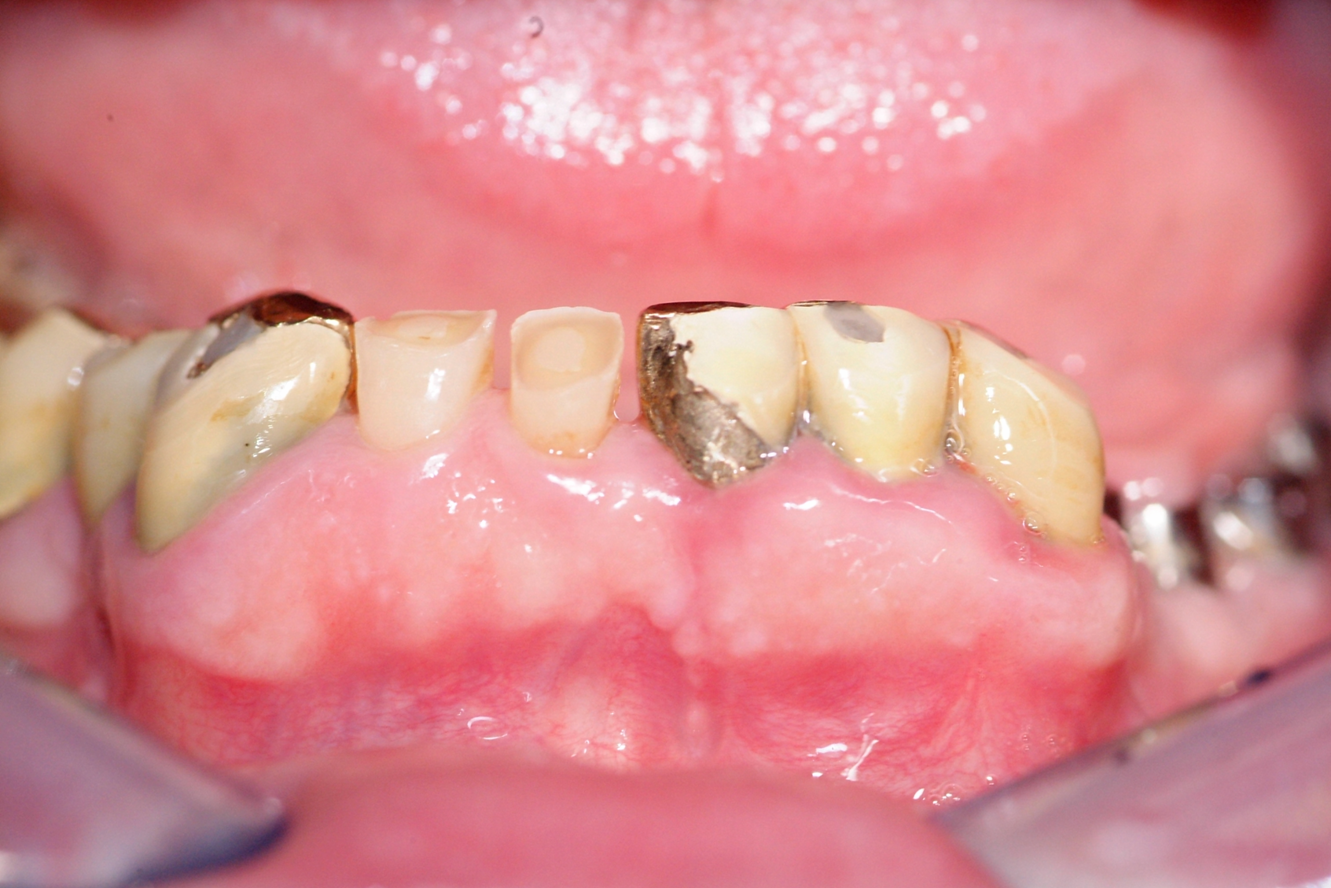

Il paziente chiede il rifacimento protesico di terapie eseguite da oltre 20 anni. Il caso comporta un trattamento multidisciplinare: endodontico, implantologico, protesico e di chirurgia osteoresettiva. Si rimodella l'osso per ridare un corretto profilo osseo e una nuova estetica al sorriso.

Riabilitazione orale delle due arcate protesi fisssa in oro ceramica dopo chirurgia osteoresettiva.